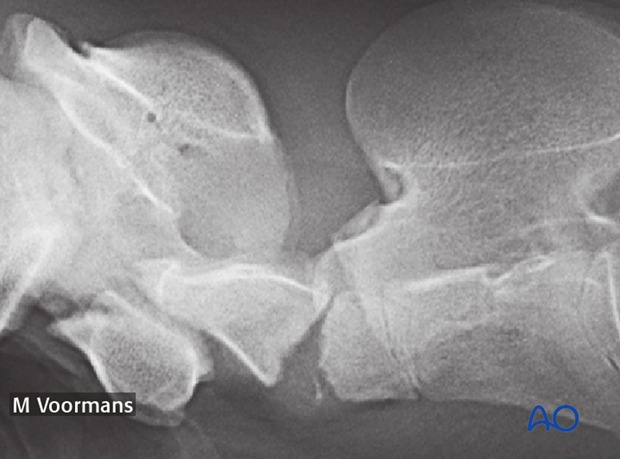

The radiograph shows the fracture of the dens in a foal.

Note: Fixation of an axial dens fracture will require atlantoaxial arthrodesis.